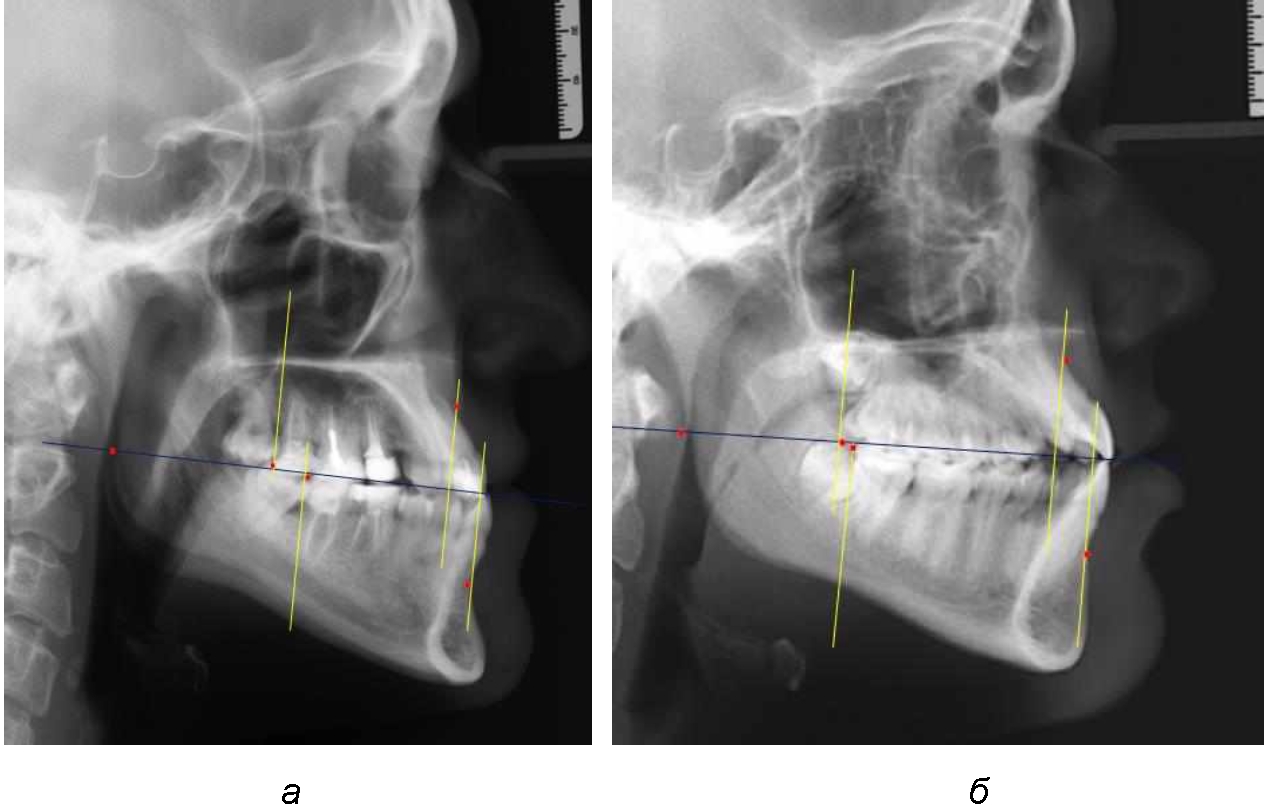

При сагиттальной патологии прикуса встречались варианты, при которых отмечалось равенство либо не равенство альвеолярно-ден-тальных размеров челюстей. Однако вне зависимости от этого, как правило, была отмечена разница в положении челюстей, измеряемая от конструируемой точки «rmРOcP» до точек апикальных базисов по Downs. С дистальной окклюзией было 20 снимков и с мезиальной окклюзией – 19 снимков.

Характерной особенностью мезиальной окклюзии было увеличение расстояния между проекционными апикальными точками, при котором существенно смещалась кпереди нижняя челюсть, а Wits-число имело отрицательные значения. Также дистальная точка нижнего моляра была расположена кпереди от верхней дистальной точки окклюзии второго моляра. Относительно равными считались показатели альвеолярно-дентальных размеров, при которых разница не превышала 1,5 мм. Тем не менее расстояние «rmРOcP-B(SM)» превышало расстояние «rmРOcP-A(SS)» в среднем по группе на (6,87 ± 1,62) мм, что свидетельствовало об аномалии положения челюстей, при котором визуально нижняя челюсть располагалась впереди верхней челюсти (рис. 3).

Рис. 3. Положение апикальных точек и челюстей при мезиальной окклюзии с равными (а) и разными (б) альвеолярно-дентальными размерами зубо-челюстных дуг

В тех случаях, когда при мезиальной окклюзии альвеолярно-дентальные размеры были различными, размер нижней челюсти превышал аналогичный параметр верхней челюсти в среднем на (3,74 ± 1,28) мм.

На рентенограммах с признаками дистальной окклюзии Wits-число имело положительные значения. Дистальная точка нижнего моляра была расположена позади верхней дистальной точки окклюзии второго моляра. Относительно равными, так же как и при анализе снимков с мезиальной окклюзией, считались показатели альвеолярно-дентальных размеров, при которых разница не превышала 1,5 мм. Тем не менее расстояние «rmРOcP-A(SS)» превышало расстояние «rmРOcP-B(SM)» в среднем по группе на (5,29 ± 1,47) мм (рис. 4).

Рис. 4. Положение апикальных точек и челюстей при дистальной окклюзии с равными (а) и разными (б) альвеолярно-дентальными размерами зубочелюстных дуг

В тех случаях, когда при дистальной окклюзии альвеолярно-дентальные размеры были различными, размер нижней челюсти превышал аналогичный параметр верхней челюсти, в среднем на (3,62 ± 1,12) мм.